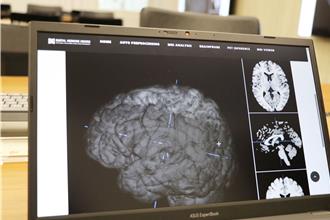

精神病診斷不靠猜!陽明交大攜手北榮 AI影像看見大腦病灶

精神疾病診斷長期依賴問診與病史,缺乏客觀量化判斷標準。為突破這一醫療困境,陽明交大與台北榮總投入腦影像與AI研究,成功開發出領先全球的腦影像分析技術。此技術能成功定位精神疾病患者在不同年齡與病程階段的腦部退化情形,且已獲臨床應用,並獲得今年美國愛迪生獎金獎(2025 Edison Awards Gold Medal)。